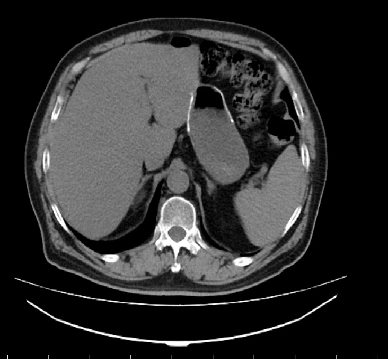

影像学检查:

胸腹盆CT:未见明显异常。 肠镜:直肠距肛门4cm见不规则肿块,约3*1.5cm,表面高低不平。

MR:1、直肠癌(T3可能),与右侧肛提肌关系密切,考虑1、炎性渗出粘连2、侵犯待排2、慢性膀胱炎3、前列腺增生。

2017-09 MR:

腹腔镜探查腹腔,见:肝脏表面,胰腺、腹腔、盆腔无肉眼可见转移结节,盆腔未见明显腹水。肿瘤位于直肠下段腹膜返折处,肿瘤侵及浆膜外,与周围组织粘连成团,冰冻骨盆。行乙状结肠造口术。

影像学复查:( XELIRI方案)

2018-01: 两肺气肿,左肾小结石,肝左叶考虑异常灌注,腹腔,盆腔未见复发转移病灶。

2018-03: 两肺气肿,两肺下叶纤维灶,肝左叶考虑异常灌注,慢性膀胱炎,前列腺钙化,盆腔未见复发转移病灶。

2018-06:肝脏局部灌注异常,实质内多发小斑片状影。

2018年06月:肝脏局部灌注异常,实质内多发小斑片状影

2018年09月平扫:未见特殊异常

胸腹盆增强CT(2020-05-08):直肠癌治疗术后,左下腹造瘘术后,肝脏多发转移较前增多增大,双肺气肿,主动脉及冠状动脉硬化,双肾囊肿